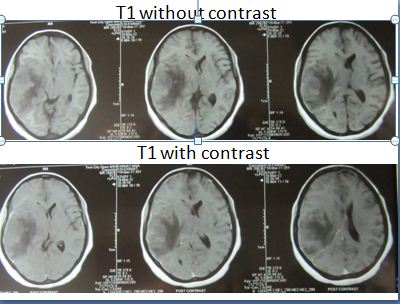

•A 35 year old female delivered a healthy baby 15 days back presented with drowsiness for 2 days. On examination she had 3/5 power on left side of body. Her MRI was performed

•What is the most likely cause of this lesion and what other imaging sequence you would be looking for?